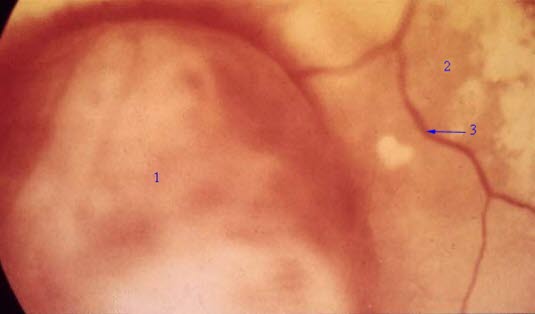

Melanom i uvea